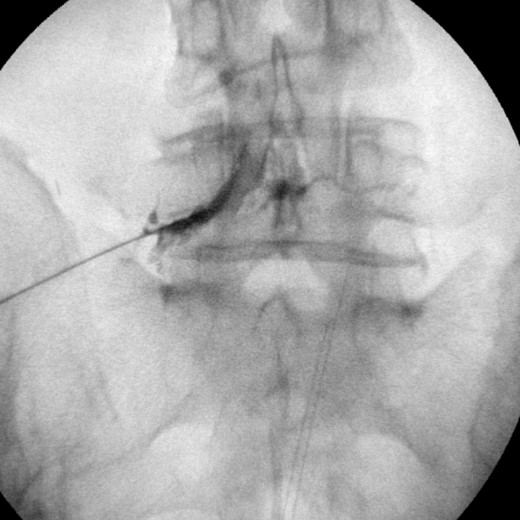

3.0.1 석회쇄척술 (barbotage)

석회쇄철술 후 사진, 시술 사진 추가